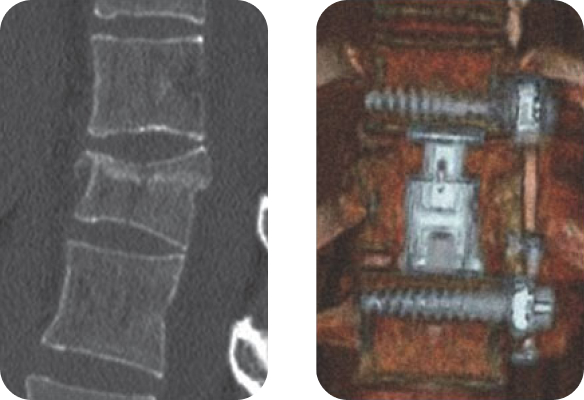

Клинический пример 1

- Неполный взрывной перелом тела L3-позвонка (А 3.1).

- Выполнена стабилизация костным материалом и пластиной GoldenGate®